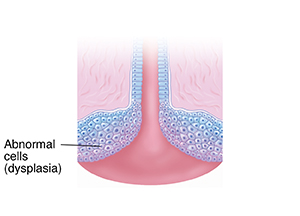

Dysplasia starts when cells on the surface of the cervix change in ways that are not normal. Cells may grow irregularly. They may become cancer.